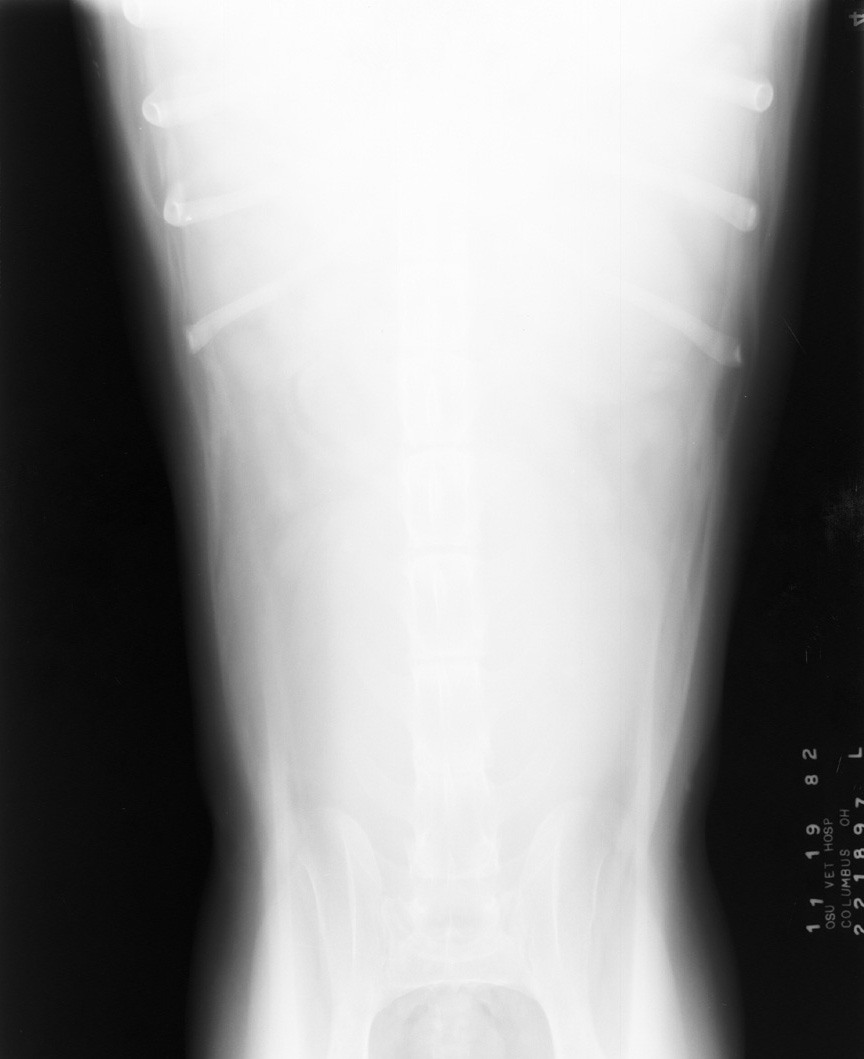

Underexposure

Underpenetration of abdomen due to radiographic underexposure (kv too low).